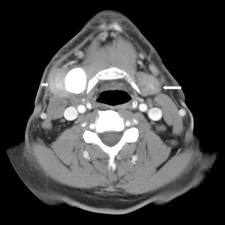

- КТ или МРТ слюнной железы;

В зависимости от диагноза, перед операцией назначаются различные исследования — УЗИ, компьютерная или магнитно-резонансная томография, рентгенография легких. В случае опухоли также необходима биопсия для выяснения характера образования. Слюннокаменная болезнь исследуется с помощью контрастной сиалографии.

Как правило, подчелюстное массовое тестирование включает в себя компьютерную томографию, а также пункцию тонкой иглой (FNA) из самой массы. Получение FNA полезно для определения степени хирургического удаления. При обнаружении злокачественности требуется более обширная хирургическая процедура, включая полное удаление железы, а также окружающих лимфатических узлов (лимфатическая очистка).